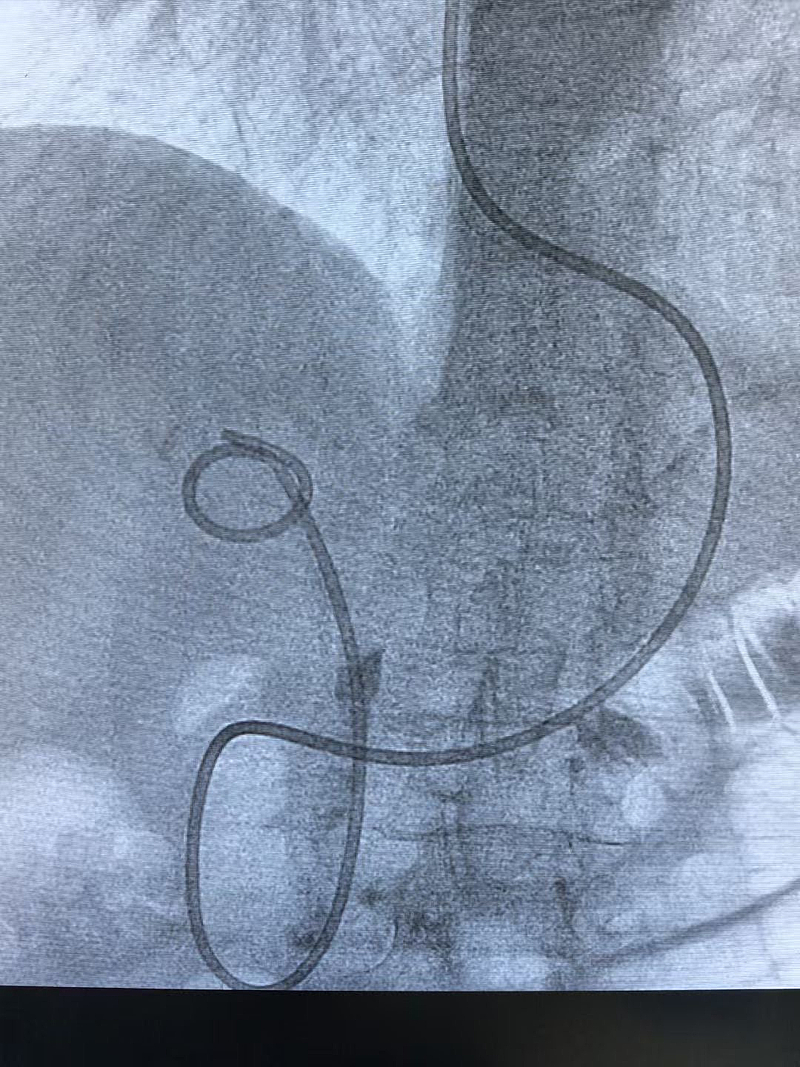

近日,延安市中医医院(北京大学第三医院延安分院)消化内科(脾胃病科)成功为一名90岁高龄患者实施了内镜下逆行性胰胆管造影术(ERCP)手术,解除了患者的病痛。

90岁的高龄患者一年前因右上腹疼痛就医,经MRCP检查确诊为胆总管结石。先后辗转市内多家医院,但由于患者高龄、手术风险大,进行保守治疗,症状却未见改善。患者家属听闻我院ERCP手术能治疗胆总管结石后,带着患者来到我院消化内科(脾胃病科)就诊。消化内科(脾胃病科)郭锐主任团队多次讨论后,为患者制定手术方案,征得患者同意后,成功实施了ERCP手术,顺利取出结石,患者康复出院。

时隔一年后,因饮食不当,患者再次出现上腹痛症状。门诊腹部超声检查显示胆囊结石合并胆总管结石,疑似结石嵌顿引发胆管炎,建议入院治疗。此次入院,患者身体机能衰退明显,除胆管炎症状外,还伴有慢阻肺、冠心病等多种基础疾病,呼吸困难与心衰症状明显。面对复杂危重的病情,我院消化内科(脾胃病科)医护团队全力以赴,精心制定治疗方案,积极纠正心衰状况,再次成功为患者实施ERCP手术。术后,老人恢复状况良好,现已顺利出院。